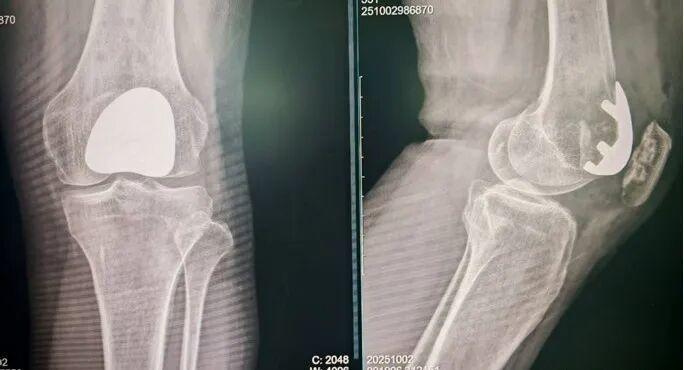

(术后影像学检查)

王廷广博士接诊后,对房女士详细检查,确诊其为髌股骨关节炎。结合患者的病情及身体状况,王廷广团队决定为其实施髌股关节置换术。在术前准备阶段,骨关节科组织了多学科会诊(MDT),邀请麻醉科、康复科等相关科室专家共同参与,对患者进行全面评估,制定了详细的手术方案。

手术当天,王廷广博士带领团队进入手术室,团队凭借丰富的临床经验和精湛技术,在麻醉科的密切配合下,精准完成了病变髌股关节的表面置换。整个手术创伤小,最大限度保留了房女士膝关节的正常结构。